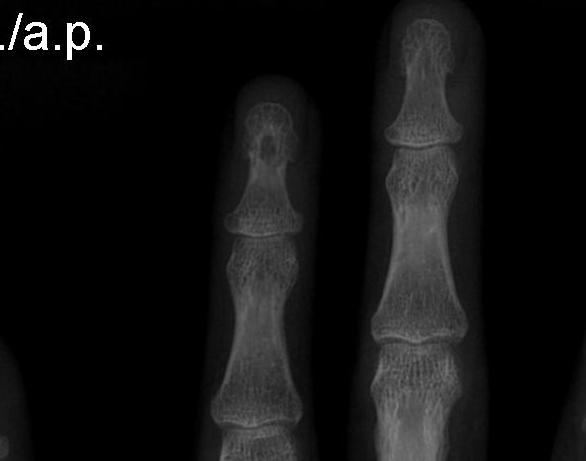

X-ray

Round / oval lesion in P3

- thinning of cortex